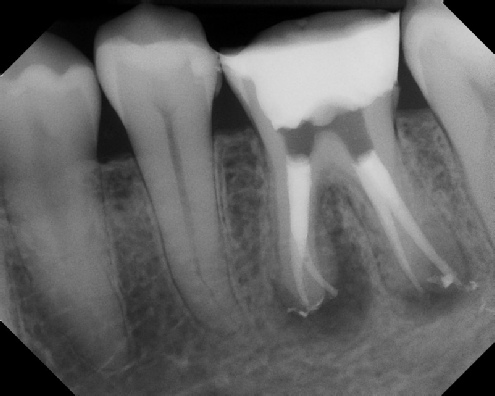

Root Canal Retreatment - Meriden 8 mos. recall Post-op Pre-op